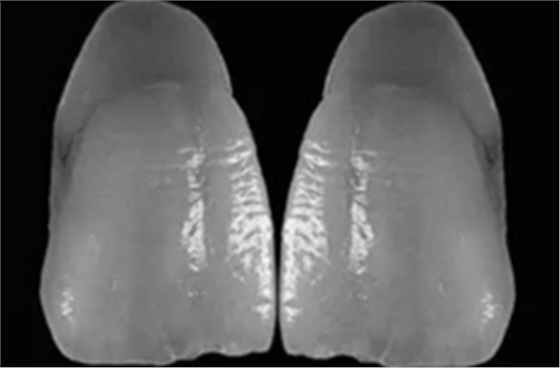

14、在工作模完全就位的義齒

15、在檢測模上可以看出左上1頸線有誤差